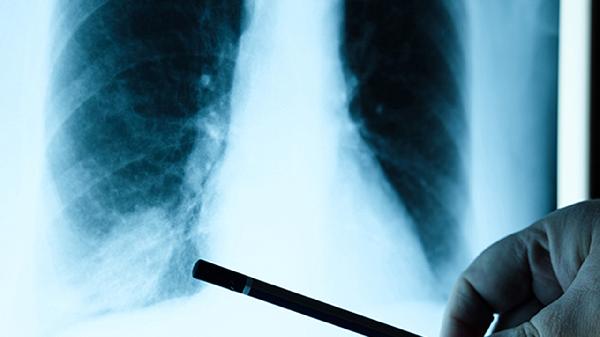

对于中大量积液或出现呼吸困难的患者,胸腔穿刺是快速缓解症状的首选方法。通过超声定位下抽取积液,既能明确积液性质如区分漏出液与渗出液,又能减轻肺组织压迫。操作后需监测血压、氧饱和度,警惕复张性肺水肿。